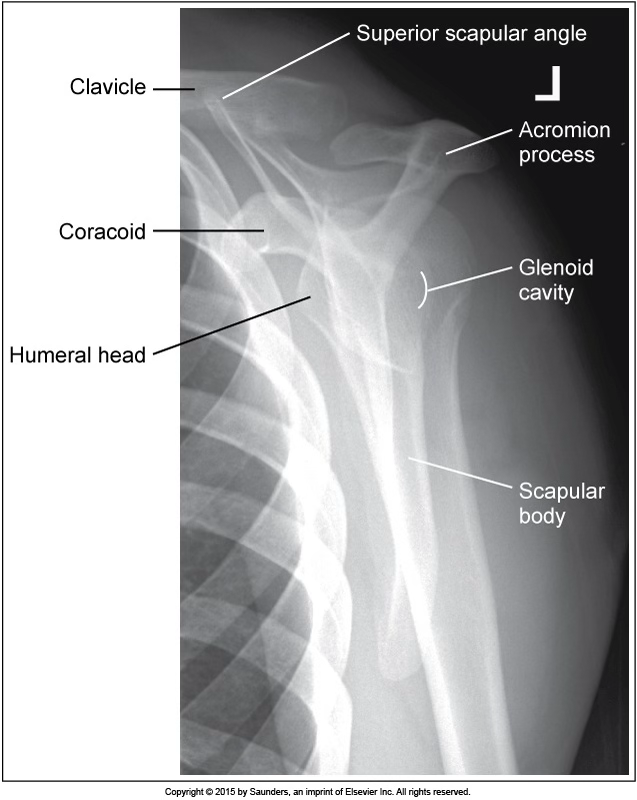

AP neutral shoulder

accurate positioning